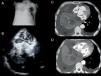

A) Radiografía de tórax: derrame pleural derecho masivo. B) Ecocardiografía transtorácica: en plano apical 4 cámaras se objetiva la existencia de una gran masa retrocardíaca heterogénea que invade las aurículas. C y D) Tomografía computarizada: se confirma la existencia de un tumor retrocardíaco que invade masivamente las aurículas en ausencia de derrame pericárdico.

AD: aurícula derecha; AI: aurícula izquierda; DP: derrame pleural; T: tumor; VD: ventrículo derecho; VI: ventrículo izquierdo.

Se presenta el caso de un varón de 51 años, fumador y enólico, que consultó a urgencias por tos, disnea y edemas en piernas, progresivos, y de 2 meses de evolución. Al examen físico destacaba la existencia de caquexia, hipofonesis pulmonar derecha a la auscultación y edemas en extremidades inferiores con fóvea; la analítica inicial y el electrocardiograma no mostraron alteraciones significativas y, radiológicamente, destacó la presencia de un derrame pleural (DP) derecho severo (fig. 1A); mediante toracocentesis se drenaron 1.800ml de un líquido pleural seroso. Para descartar el origen cardiogénico del cuadro se realizó una ecocardiografía (fig. 1B), detectándose la existencia de una masa retrocardíaca heterogénea (siendo esto sugestivo de la existencia de necrosis y/o hemorragia intratumoral) de 11,8×11cm de diámetro; dicha masa invadía las tres cuartas partes de la cavidad de la aurícula izquierda (AI), quedando abolido el drenaje de la vena pulmonar inferior derecha (VpID), y casi la mitad de la de la aurícula derecha (AD), y presentaba masas móviles en superficie; también se documentó hipertensión pulmonar, elevación de la presión venosa central y la ausencia de derrame pericárdico. La tomografía computarizada (figs. 1C y D) confirmó la existencia de un DP derecho severo, e izquierdo mínimo, y de un gran tumor pulmonar que ocupaba el lóbulo inferior derecho (LID) y englobaba y colapsaba el bronquio intermediario y sus ramas; dicho tumor era heterogéneo y obliteraba gran parte de la AD, pero casi la totalidad de la AI, constatándose la ausencia de permeabilidad de la VpID.